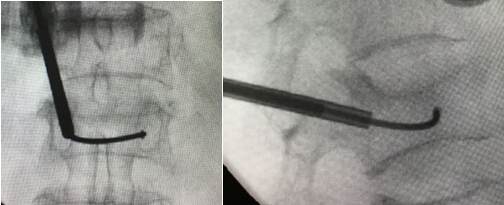

专用的弯角椎体成形装置

术中正侧位透视显示弯角的注射管